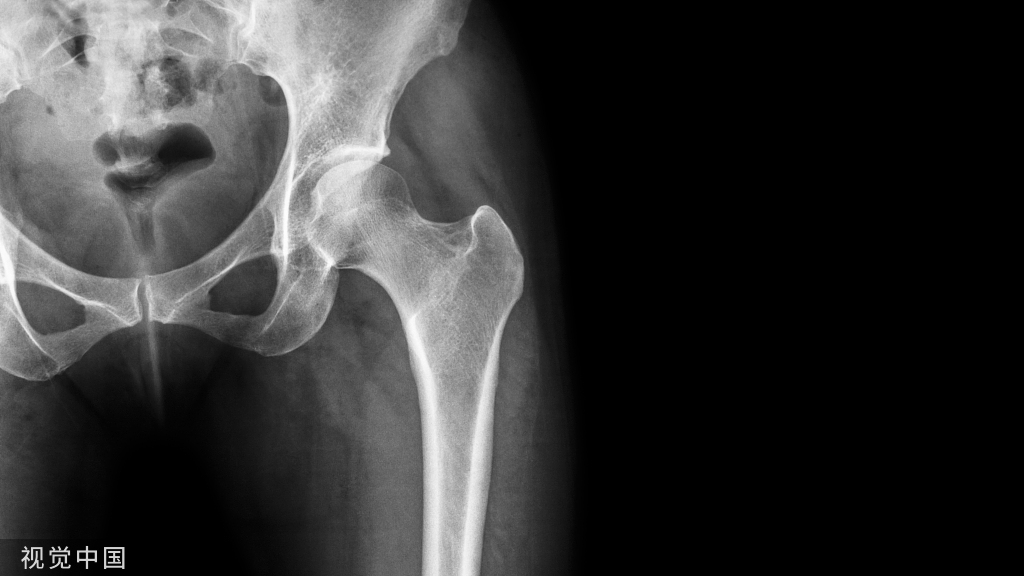

三、x线检查

匹配关节

不匹配关节

1.拇外翻角(HVA):第一跖骨纵轴线与第一趾近节趾骨纵轴线之夹角,正常 < 20°。

2.跖骨间角( IMA):第一、二跖骨纵轴延长线之夹角,正常6°~12°。

3.趾骨间角(IPA):第一趾近节趾骨与远节趾骨纵轴延长线之夹角,正常11°~18°。

4.近侧关节固定角(PASA):第一跖骨远侧实际关节面连线的垂线与该骨纵轴线之夹角,正常3°~8°。

5.远侧关节固定角(DASA):第一趾近节趾骨近侧实际关节面连线的垂线与该骨纵轴线之夹角,正常1°~7°。

6.跖楔角(MCA):第一跖骨近侧实际关节面连线的垂线与其纵轴线之夹角,正常6°~15°。

7.跖骨内收角(MAA):在跗骨内外侧缘的连线上各作中点;然后把两点连成线,在此线上作垂线,垂线与第二跖骨纵轴延长线之夹角,正常8°~12°。

8.第一、二跖骨远端长度差:正常情况下第二跖骨稍长于第一跖骨约2mm。

9.籽骨位置:可通过胫侧籽骨在第一跖骨平分线的位置确定胫侧籽骨的位置,共分7种,第一种为正常,2~7示向外移位的程度。

10.足负重与非负重位X线片测量:除HVA外,负重位IMA等均大于非负重位。